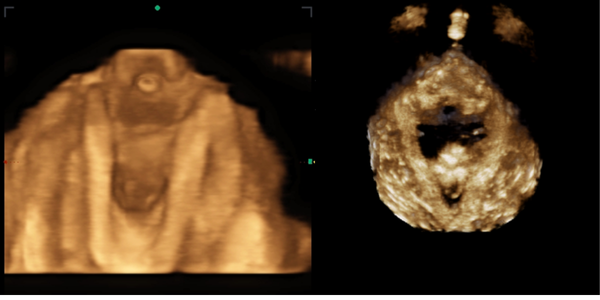

Ahora damos un paso más, además de la ecografía funcional en 2D introducimos la ecografía funcional en 4D. Este tipo de ecografía nos permite ver las estructuras anatómicas con volumen en tiempo real y calcular áreas anatómicas concretas, lo que amplia nuestras posibilidades de valoración y potencia nuestros resultados.

Mediante la ecografía funcional en 4D podemos valorar esta capacidad funcional en cada mujer para detectar aquellas mujeres que necesitan reeducar esta función antes del parto y con ello minimizar los riesgos. La reeducación se basa en el uso de la ecografía como sistema de biofeedback, consiguiendo que cada mujer sea capaz de realizar pujos de forma eficaz y segura.

Sumada a toda la información de la ecografía funcional en 2D, añadimos la información que nos aporta la ecografía funcional en 4D respecto a los músculos del suelo pélvico y los esfínteres Podemos observar la respuesta de los tejidos en tiempo real, conocer las medidas morfométricas de los músculos del suelo pélvico, la posición de los músculos dentro de la pelvis menor, la posición de la vejiga, el recto, el útero, la capacidad vesical, el control motor etc.